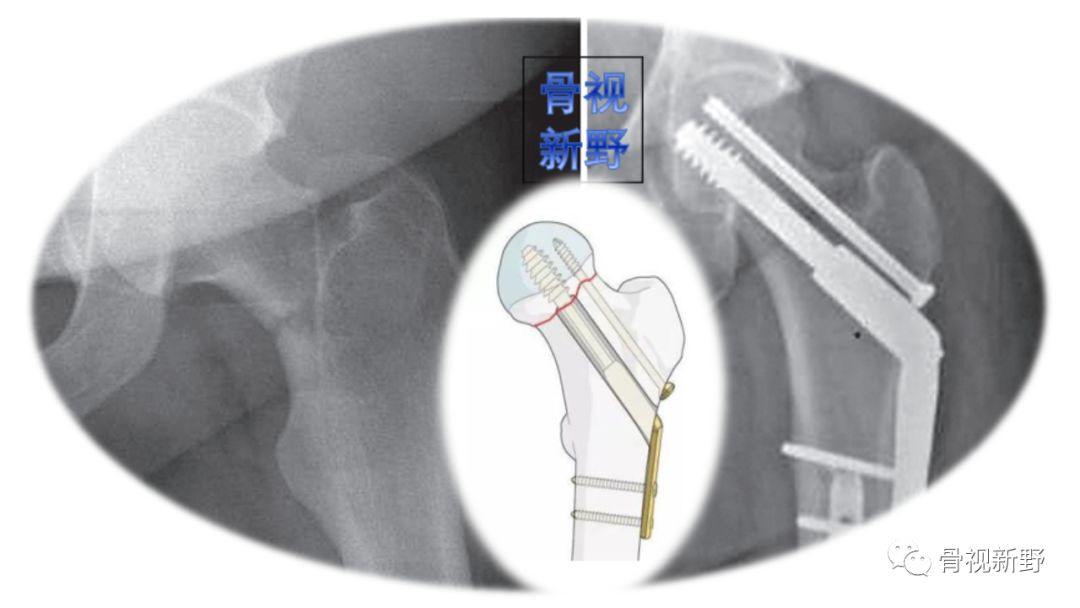

优化固定新理念——双平面固定(又称“F”固定技术) (biplane double-supported screw fxation,BDSF技术)

螺钉分布在前后位X线片呈字母“F”形而得名。

优 点

A. 远端空心钉大角度强斜置人,增加了股骨干支撑处的力臂,保证了两支撑点间足够大的距离,从而降低两支撑点的压力负荷(如下图示):

B. 双支撑点、双平面固定具备较强的抗压和抗剪力作用,生物力学性能优越,尤其适用于骨质疏松患者(如图示):

C. 增加了螺钉间距,有效避免应力集中,降低螺钉退出、断裂等风险。

缺 点:

A. 螺钉置入有一定难度,沿股骨颈切线置入时有损伤皮质导致医源性骨折的风险。

B. 在股骨头内分散的螺钉置入有增加股骨头缺血性坏死的风险。